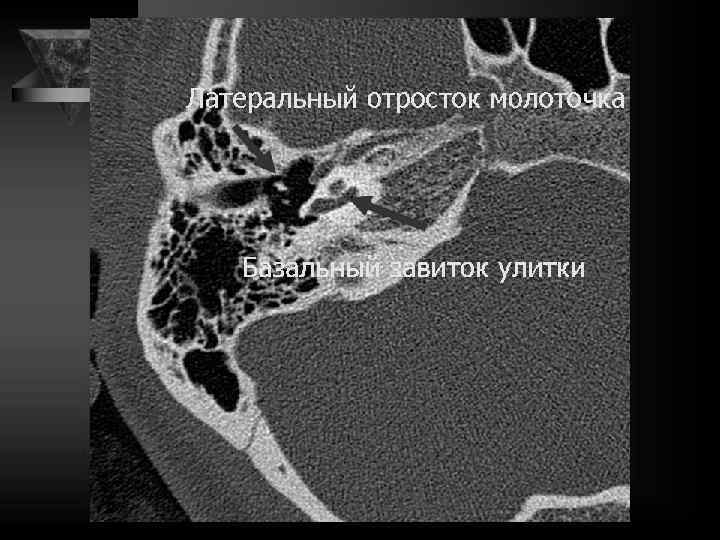

Молоточек 2 головка 3 шейка 4 рукоятка 5 передний отросток 6 латеральный отросток